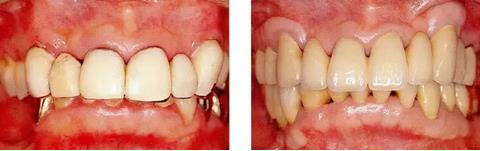

圖17-3(左) 為了獲得足夠的附著牙齦,在下頜前牙區(qū)進行free gingival graft。讓游離齦移植片不要移動地進行緊密的縫合。

圖17-4(右)進行free gingival graft 4年后的狀態(tài)。刷牙時無疼痛,牙齦也無退縮。